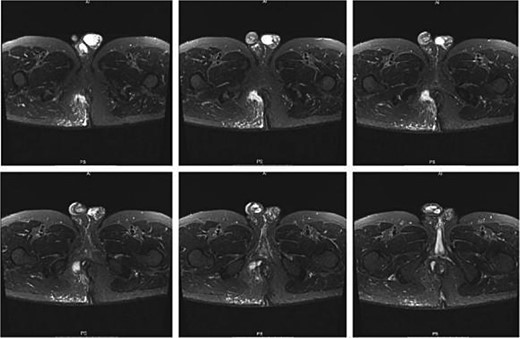

A 61-year-old male presented to our facility with a chief complaint of ‘perianal protruding mass and pain for 6 days.’ His medical history was unremarkable for hypertension, diabetes mellitus, and hematological disorders. Notably, the patient had a history of perianal abscess surgery 2 years prior to presentation. Perianal magnetic resonance imaging (MRI) findings indicated a high perianal abscess involving the right anal space, right ischiorectal fossa, and right gluteal flap, which was considered a new development. An old sinus tract in the posterior perianal space with fibrous tissue formation on the posterior wall of the anal canal was also observed, suggesting a correlation with the patient’s medical history (Fig. 1). Comprehensive laboratory assessments, including complete blood counts, liver function tests, renal function tests, coagulation profiles, electrolyte panels, infectious disease screenings, and electrocardiograms, were all within normal limits.